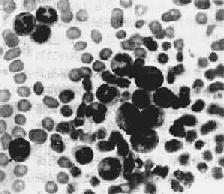

(1)血象:白細胞數常>50×109/L有時可達500×109/L以上約1/3患者血紅蛋白<110g/L貧血多為正常細胞正色素性。血小板往往增多,有時高達1000×109/L,少數病人可正常減少血塗片檢查中可見不同成熟階段的粒細胞以中晚幼粒細胞階段居多原料細胞<5%,原粒+早幼粒細胞≤10%,嗜酸性及嗜鹼性粒細胞增多,有少量有核紅細胞出現

(2)骨髓象:增生極度活躍或明顯活躍,以粒係為著粒與紅之比可增至10∶1~20∶1粒系各階段均增加,以中、晚幼粒細胞增加為主。嗜酸性與嗜鹼性粒細胞比例明顯高於正常巨核細胞及血小板亦增多